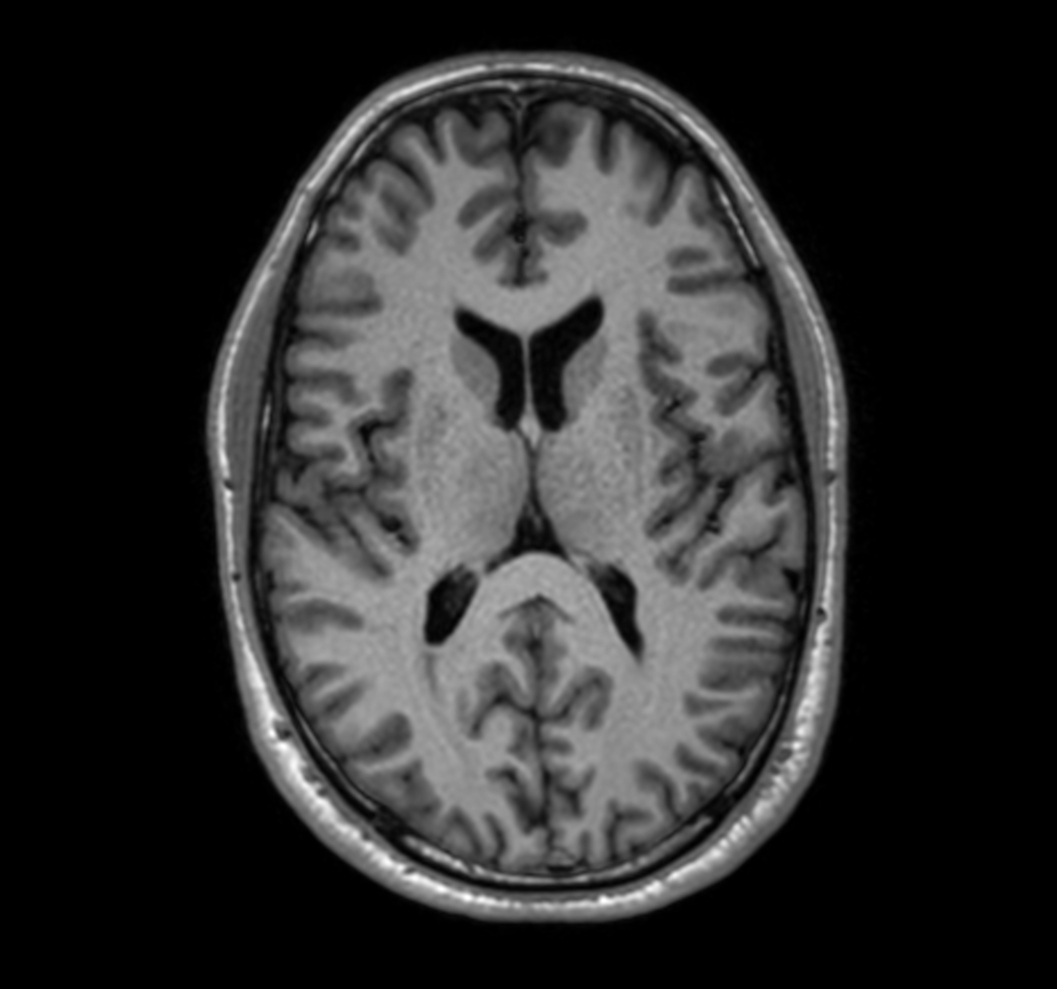

3D T1w TFE with ComforTone (axial reformat)